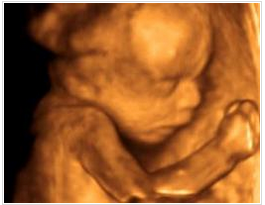

醫(yī)生一邊給醫(yī)生助理報(bào)數(shù)據(jù),一邊耐心的為我講解,哪里是寶寶的手啊腳啊,之后我們又聽(tīng)到了臍血流和胎心音,醫(yī)生說(shuō)寶寶的身體很健康,一切都正常,我這才放心下來(lái)。整個(gè)四維彩超檢查過(guò)程大約持續(xù)1個(gè)小時(shí),可我仍覺(jué)得意猶未盡,期間還把寶寶的萌照拍了下來(lái),是不是很可愛(ài)呢?

做四維彩超所看到的胎兒在宮內(nèi)的情況